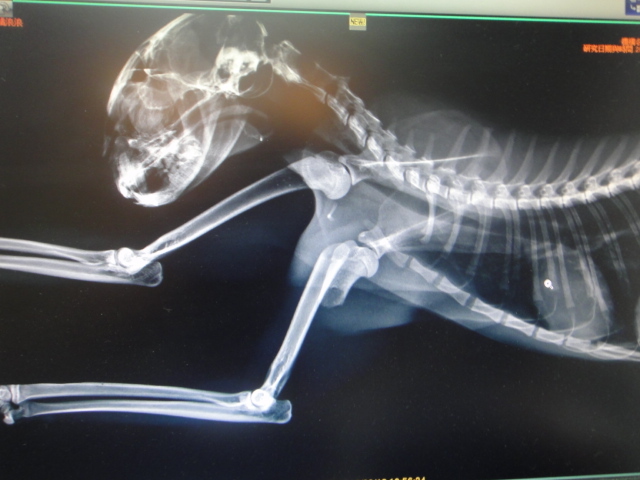

主題: 小橘貓的腳斷了 申請者姓名: 陳小玲 花色: 申請日期: 2012-10-11 22:42:19 申請者部落格: 申請者臉書網址: 所在縣市/合作醫院: 台南市/豪斯動物醫院 治療費用: 13500元 需求人數: 15人 已結案 (2013-06-27 13:48:11) 報名人員: Sandymimi Ng、蔡甫(已付款)、王璇華(已付款)、chiawei(已付款)、豆漿(已付款)、小珍(已付款)、林力紗(已付款)、Sofie Lin(已付款)、Julia(已付款)、Christine Chao(已付款)、小節(已付款)、May Chuang(已付款)、高小玉(已付款)、ailsa(已付款)、ailsa(已付款)、sandy_huanglichuan(已付款)、 候補人員: 動物病情說明: 小橘是我餵養的浪貓之一,牠十天沒出現,再出現時我就將牠捕捉去結紮,我發現牠的腳怪怪的,請醫生照了x 光後才發現小橘的腳斷了,當天就轉送到台南的豪斯動物醫院,在醫院待了快三星期,在10月1 日接回嘉義自己照顧,醫生說小橘還要在照顧三星期,但腳的靈活度沒辦法和以前一樣,不適合再野放,所以,等小橘好了,再幫牠找看看是否有人願意領養牠.